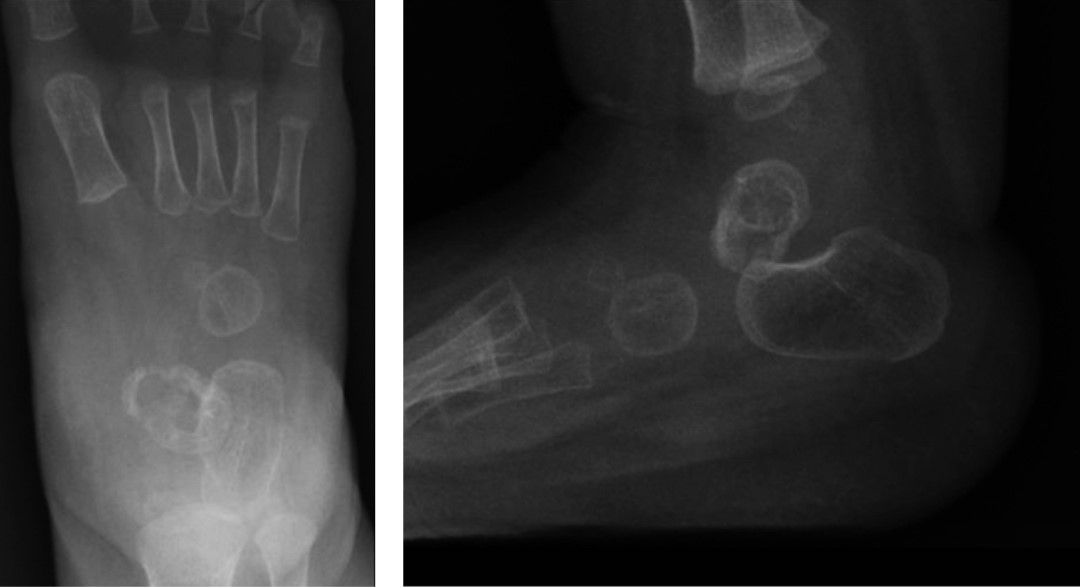

Figura 1